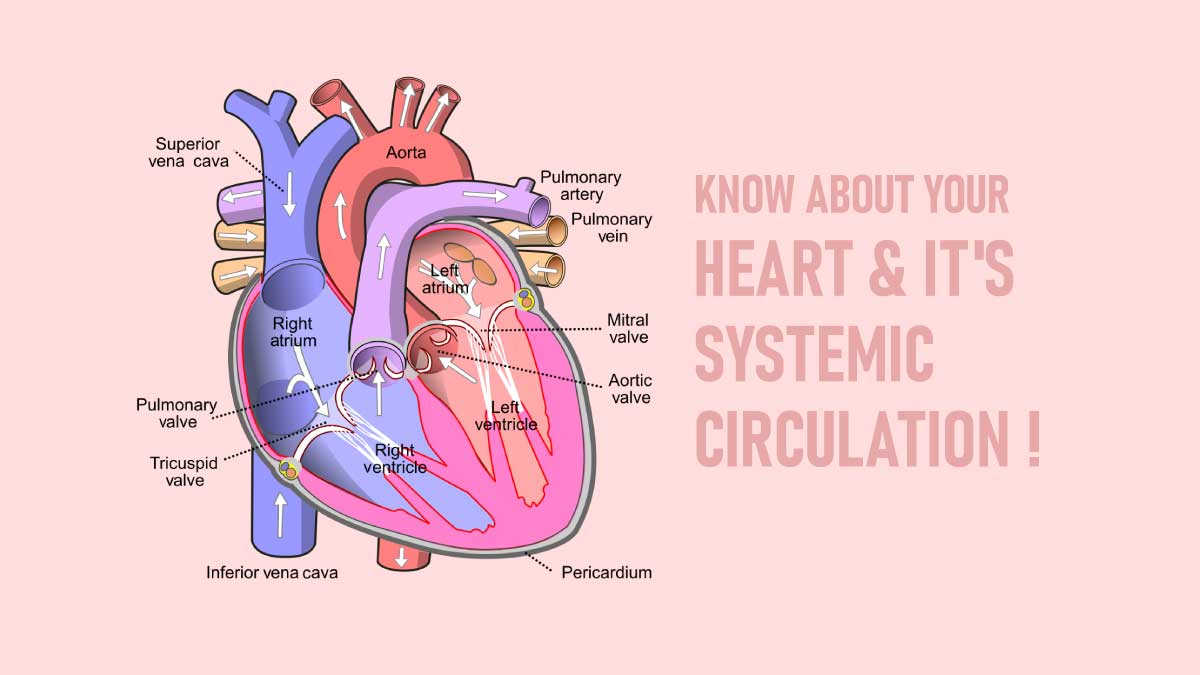

Right atrium

It is the right upper chamber of the heart.Right atrium forms the right border, part of the upper border, the sternocostal surface, and part of the base of the heart . It receives blood from the entire body and pumps it to the right ventricle through the right atrioventricular or tricuspid orifice[opening].

Right Ventricle

The right ventricle forms the inferior border and a large part of the sternocostal surface of the heart. It is a triangular chamber. The pulmonary trunk and pulmonary arteries take deoxygenated blood from the right atrium and pump it to the lungs.

1. The right atrioventricular orifice or tricuspid orifice, guarded by the tricuspid valve.

2. the pulmonary orifice is guarded by the pulmonary valve.

Left Atrium

It is a quadrangular chamber receiving oxygenated blood from the lungs through four pulmonary veins and pumps to the left ventricle through the left atrioventricular or bicuspid or mitral orifice, which is guarded by the mitral valve[bicuspid valve].

Left Ventricle

The left ventricle gathers and pumps oxygenated blood from the left atrial into the aorta.

The interior of the ventricle shows two openings:

1. The left atrioventricular or bicuspid, or mitral orifice is guarded by the mitral valve.

2. The aortic orifice, guarded by the aortic valve.